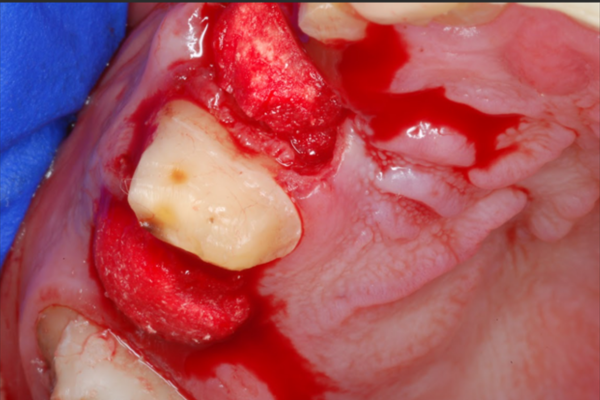

A jaw after bone grafting surgery.